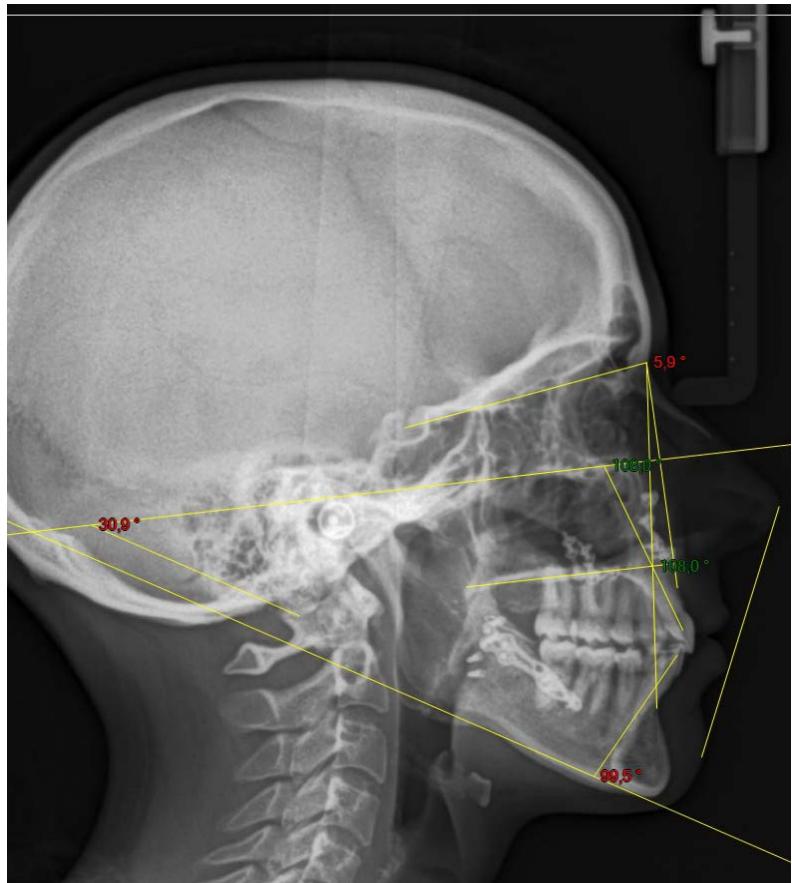

L'examen cephalométrique confirme le diagnostic de classe II squelettique par rétromandibulie et la forte vestibulo-version des incisives mandibulaires $(112^{\circ})$.

Examen cephalométrique de début de traitement.

La comparaison des télé radiographies permet d'objectiver le redressement incisif mandibulaire et la distalisation molaire mandibulaire obtenue. Nous observons également le maintain des axes incisifs au niveau de l'arcade maxillaire.

On note un redressement incisif très important. En effet, l'axe incisif mandibulaire est passé de $112^{\circ}$ à $90.3^{\circ}$ en 6 mois. Une distalisation molaire de 3 MMA également été obtenu. Les axes incisifs maxillaires ont été maintainus, ce qui correspond parfaitement à notre objectif de départ.

Télé radiographies de profil: comparaison entre l'image de début de traitement et l'image de contrôle après 6 mois de traction sur l'ancrage par fil dans la branche montante mandibulaire. L'angle incisif est passé de 112 à $90,3^{\circ}$.